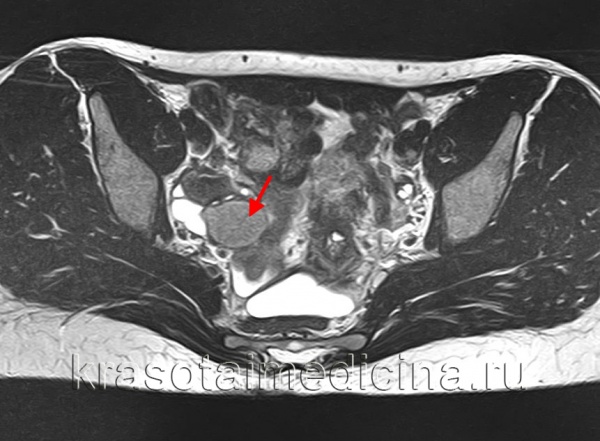

(Слева) КЖТ часто осложняется кровоизлиянием (отмечено калиперами). Геморрагическая КЖТ может иметь УЗ-картину в виде кружевного узора, а также тонкие перегородки, и обычно регрессирует спонтанно, что и визуализируется по данным трансвагинального УЗИ яичника в В-режиме.

(Справа) В этом случае КЖТ, тщательная оценка задней стенки кисты выявляет наличие уровня «жидкость-взвесь». Визуальная картина соответствует регрессирующей геморрагической кисте.